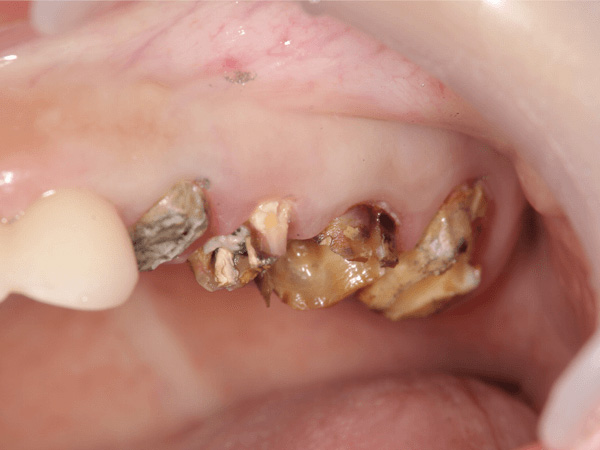

盲点であるのは、過去にむし歯治療をした歯です。一見キレイに銀歯が入っているように見えます。しかも銀歯で全周覆われているので、むし歯菌が歯に侵入しないように思えますが、実際はどうでしょうか?

金属のかぶせを外すとこのようにむし歯でボロボロになってしまっているのがわかります。なぜこのようになってしまったかというと、歯と金属のかぶせ物の間に隙間があったからです。むし歯菌は目に見えないほど小さく、むし歯菌の侵入を防ぐには、精度の高いかぶせ物を作る必要があります。